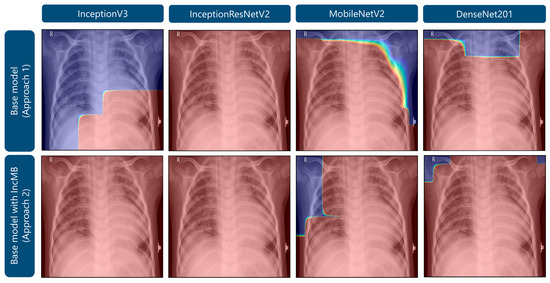

| Transfer Deep Learning Model | Classification Approach | Accuracy | F1-Score | Precision | Recall | Specificity |

|---|---|---|---|---|---|---|

| InceptionV3 | Base model | 0.9633 | 0.9529 | 0.9592 | 0.9471 | 0.9117 |

| Base model with IncMB | 0.9710 | 0.9630 | 0.9659 | 0.9603 | 0.9369 | |

| InceptionResNetV2 | Base model | 0.9676 | 0.9595 | 0.9536 | 0.9659 | 0.9621 |

| Base model with IncMB | 0.9812 | 0.9761 | 0.9781 | 0.9742 | 0.9590 | |

| MobileNetV2 | Base model | 0.9113 | 0.8961 | 0.8763 | 0.9322 | 0.9779 |

| Base model with IncMB | 0.9582 | 0.9451 | 0.9640 | 0.9297 | 0.8675 | |

| DenseNet201 | Base model | 0.9676 | 0.9579 | 0.9704 | 0.9470 | 0.9022 |

| Base model with IncMB | 0.9727 | 0.9656 | 0.9629 | 0.9684 | 0.9590 |